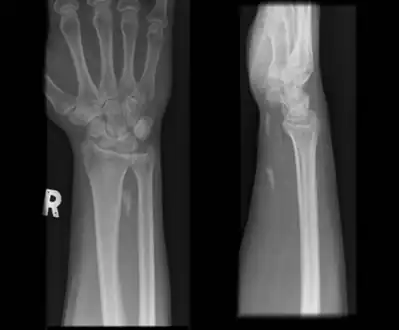

Radiographs of wrist demonstrating Calcific tendonitis of flexor carpi ulnaris. -